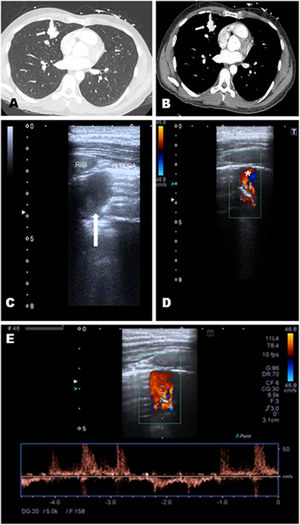

A-33-year-old man, with family history of Rendu–Osler–Weber syndrome, presented with seizures. Brain tomography showed a parietal brain lesion, and chest tomography reported a hyperdense nodular image in the right middle lobe. Lung point of care ultrasound (POCUS) was performed, and a round hypoechoic image with anterograde and retrograde flows was shown (Fig. 1), which moved with the ventilatory pattern. CT pulmonary scan revealed a dilated vascular structure in a coiled arrangement in the right middle lobe with multiple pulmonary arterial branches directly communicating with the pulmonary veins, compatible with complex pulmonary arteriovenous malformation (PAVM). Brain biopsy revealed a brain abscess, so antibiotics were started. Later, he was referred for angioembolisation.

Lung CT revealed a dilated vascular structure in the right middle lobe close to the pleura (A and B, white arrow), compatible with PAVM. Pulmonary echography showed a right parasternal hypoechoic image with an intraluminal hyperechoic area, compatible with thrombosis (C, white arrow). Doppler mode revealed a ‘mosaic-pattern’ indicative of mixing of arterial and venous blood consistent with PAVMs (D). Here, the anterograde and retrograde flow form a “ying-yang sign” (asterisk). Pulsed doppler image demonstrated arterial and venous flows (E).

PAVMs are rare, abnormal low resistance vascular structures that connect a pulmonary artery to a pulmonary vein, resulting in an intrapulmonary right-to-left shunt. The preferred screening test for PAVM is transthoracic contrast echocardiography, while thin section CT scanning is the imaging of choice to diagnose a PAVM.1 However, under certain circumstances, lung POCUS can demonstrate PAVMs. Pulmonary ultrasound perform with a good acoustic window can detect vascular malformations close to pleura, or only partially embedding the parenchyma.2 POCUS is a useful tool to rule out differential diagnosis of pulmonary images.